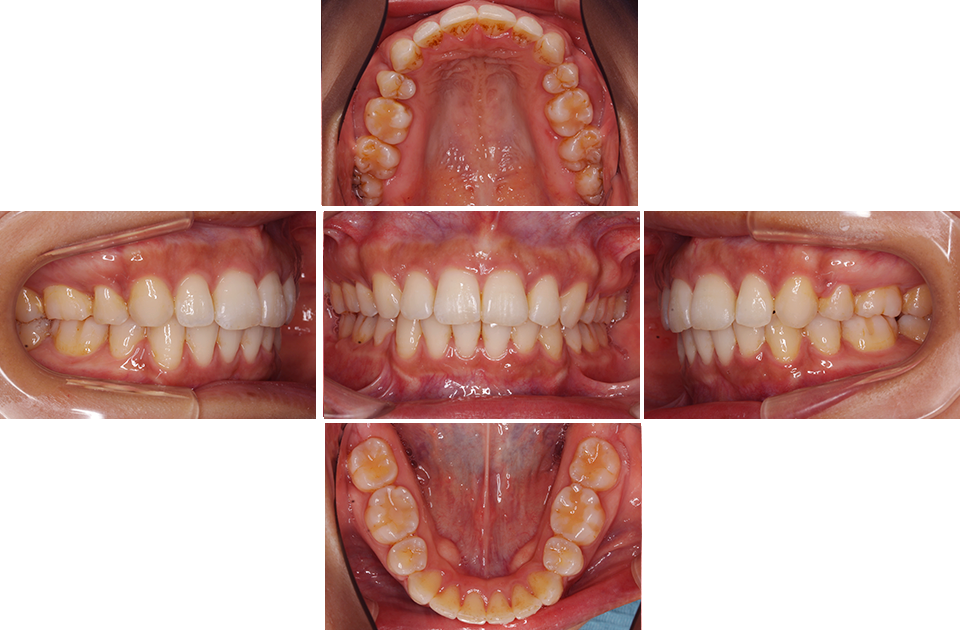

矯正前

矯正前 上顎

矯正後 上顎

矯正前 下顎

矯正後 下顎